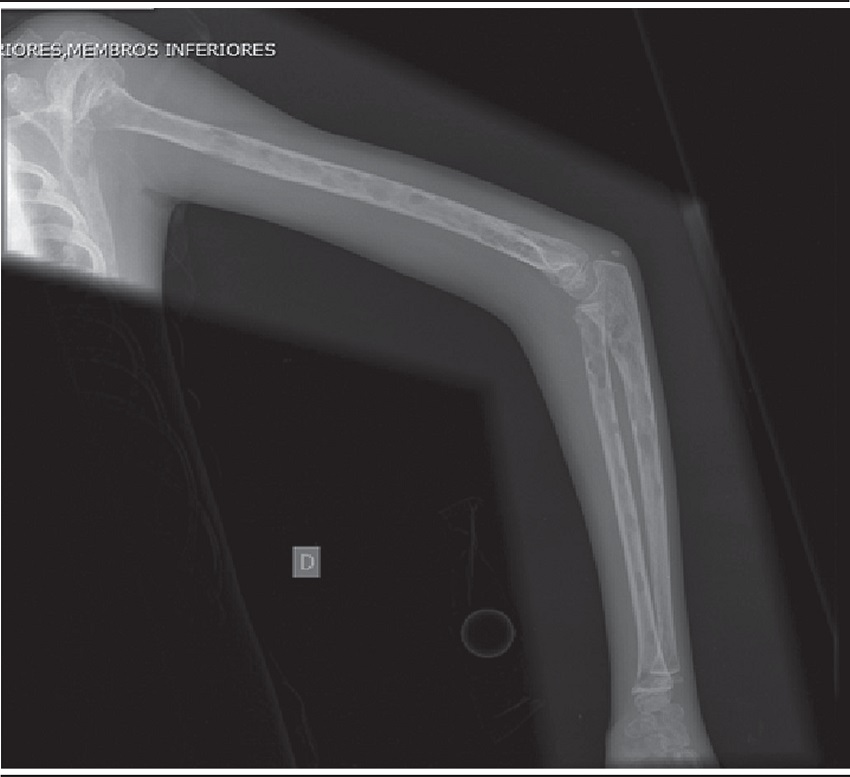

An 8-year-old girl was admitted to the pediatric emergency with bone and abdominal pain associated with vomiting, fever, and headache. Initial laboratory tests showed anemia and hypercalcemia (calcium determination of 17.8 mg/dl, reference value: 8.4-10.2 mg/dl), with average levels of parathyroid hormone. Bone radiographs showed osteolytic lesions in upper limbs, lower limbs, skull and vertebrae (Figure 1). Bone marrow aspirates, biopsies of lytic bone lesions and assessments by flow cytometry were not representative for diagnostic analysis.

Radiological image shows multiple lytic bone lesions in the right upper limb.